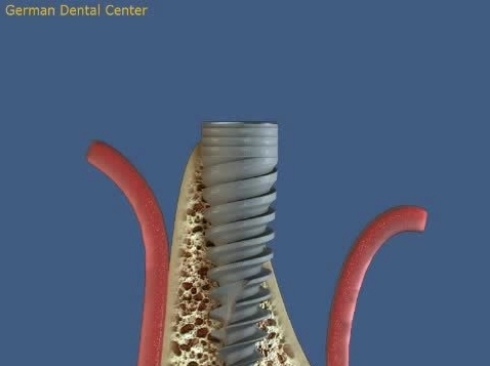

- Имплантация